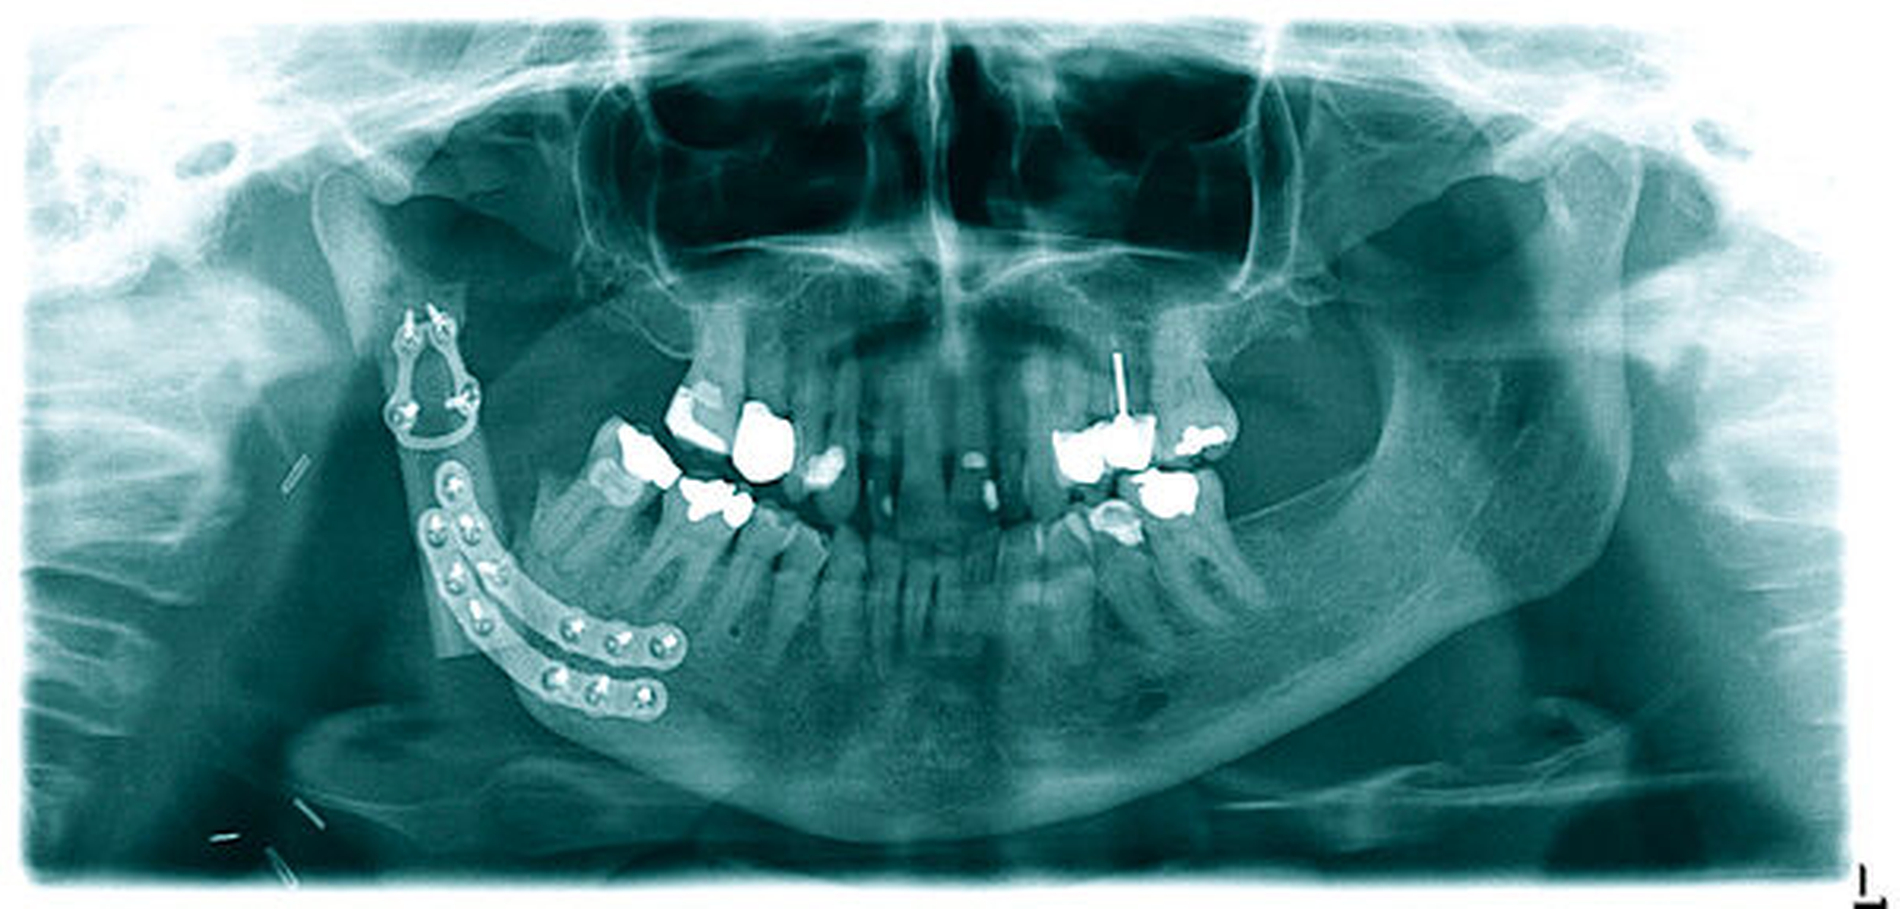

Über einen submandibulären, nach kranial bis präaurikulär extendierten Zugang erfolgte die Exploration des rechten Unterkiefers vom Kieferwinkel bis zum Proc. condylaris. Abbildung 3 zeigt die rechte Kieferwinkelregion mit dem bereits freigelegten Nervus alveolaris inferior. Eindrücklich kommen die zystisch-osteomyelitisch affektierten Lakunen im Bereich der äußeren Kortikalis zur Darstellung. Nach erfolgter Lateralisation des Nervus alveolaris inferior wurde die Kontinuitätsresektion des Unterkiefers von regio 048 bis unmittelbar unterhalb des Proc. condylaris vorgenommen (Abbildung 4). Die histopathologische Aufarbeitung des Resektats bestätigte die Diagnose einer chronischen Osteomyelitis. Der entstandene knöcherne Defekt wurde unmittelbar mit einem an die Facialisgefäße mikrochirurgisch-reanastomosierten Fibula-Transplantat rekonstruiert (Abbildung 5).